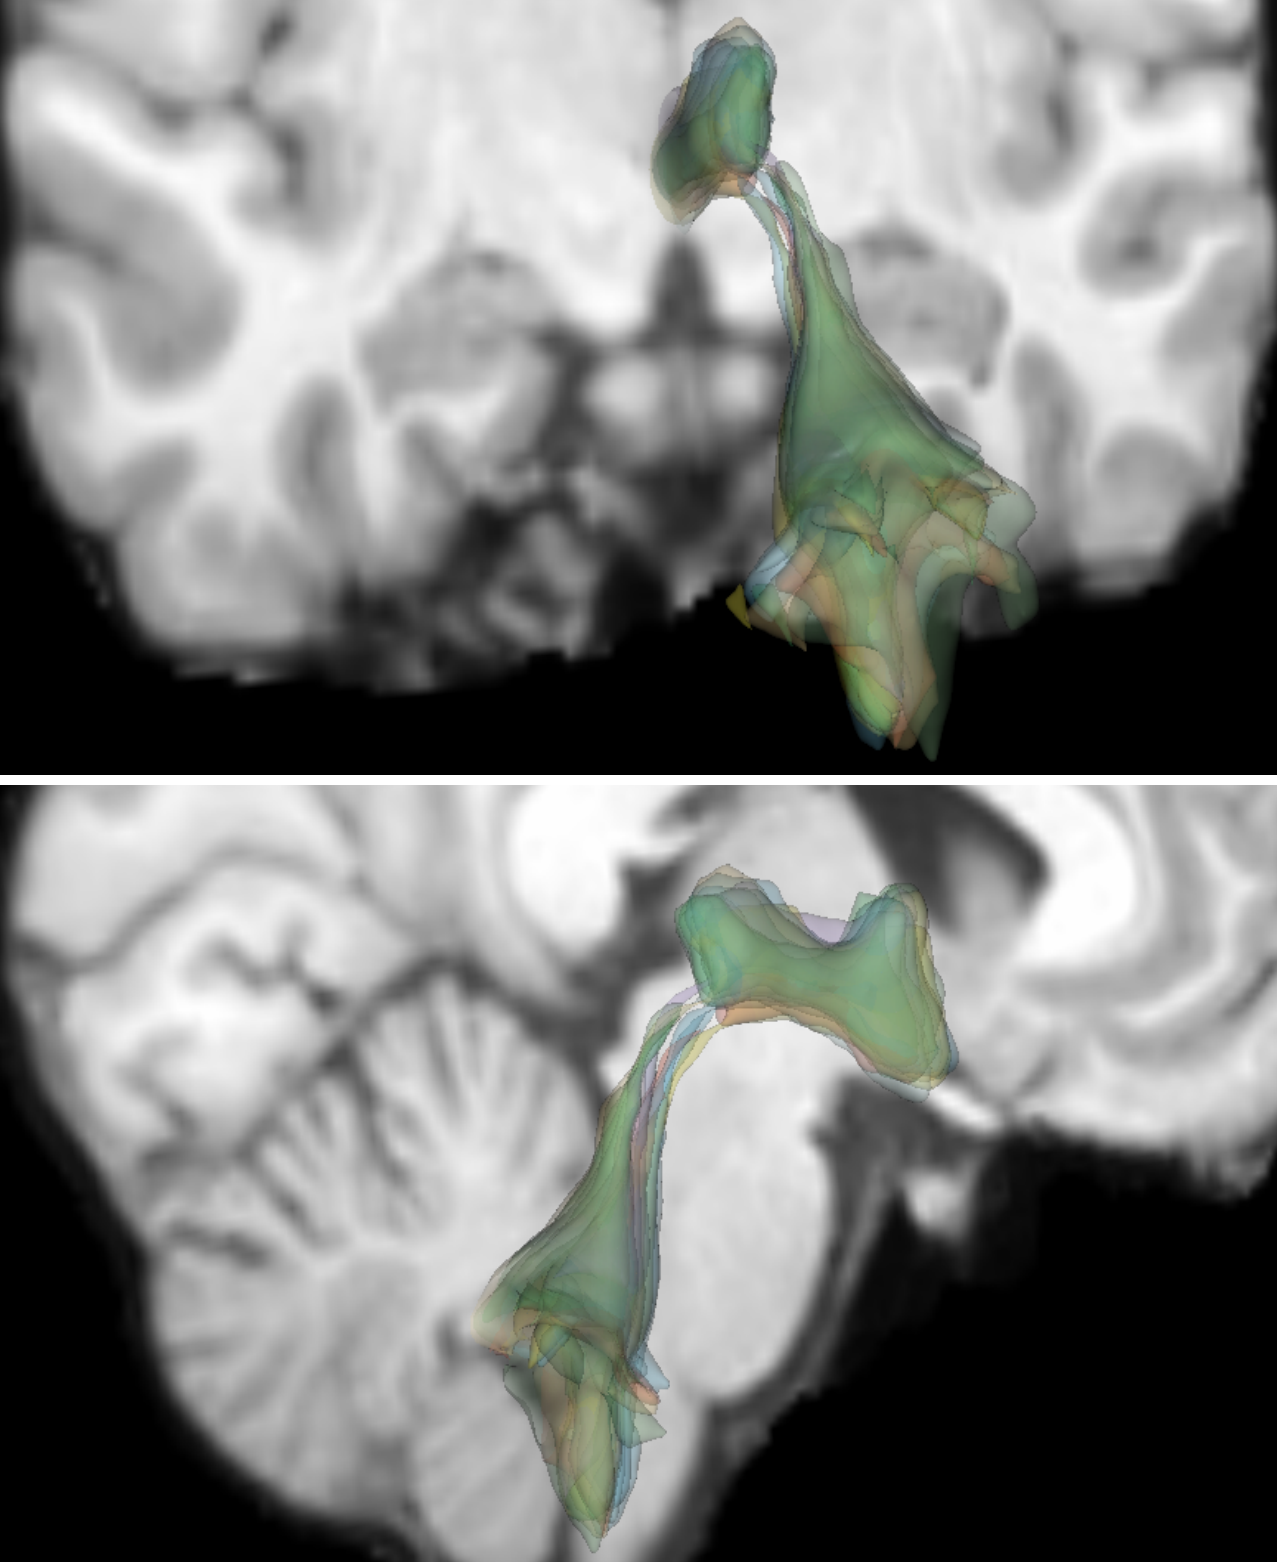

[Spaghetti plots of hippocampus on 2D slices (20 members)]

[3D spaghetti plots of hippocampus]

[3D contour plots of hippocampus]

[Spaghetti plots of ventricles on 2D slices (20 members)]

[3D spaghetti plots of ventricles]

[3D contour plots of ventricles]

5.2 IXI Dataset

Our method can be used to effectively process 3D binary masks using the binary specialization of GPU PID-mean. Examples are shown for the publicly available Information eXtraction from Images (IXI) dataset [antonelli2022medical]222https://brain-development.org/ixi-dataset/. Specifically, we use 400 T1-weighted MRI volumes of size .

For structure-specific analysis, we consider the segmentation labels of the hippocampus (Fig.˜9(a, b, c)) and the third and fourth ventricles (Fig.˜9(d, e, f)). Binary contours of a few members are visualized as spaghetti plots on 2D slices (Fig.˜9(a, d)) and as 3D isosurfaces (Fig.˜9(b, e)). These spaghetti plots reveal the fine structures of the contours but are already cluttered, especially for the 3D cases, which suffer from severe occlusions.

Clear visualizations are achieved with 3D contour boxplots generated from the PID-mean outputs. Contour boxplots of the hippocampus (Fig.˜9(c)) reveal the high agreement between the envelope of 50% (orange) members and 100% members (blue), and the median member (yellow) shows the representative shape and size of the ensemble. While for the ventricles, contour boxplots (Fig.˜9(f)) show that there is visible space between the envelope of the 50% members and that of the 100% members, the median member reveals the typical ventricles of the ensemble. Regions inside the interior surfaces are small, indicating that variations between members are rather large.

PID-mean helps gain insights into the trends of complex anatomical structures within the binary contour ensemble. The example demonstrates that PID-mean has the potential for analyzing specific medical problems in cohort studies using ensembles of medical images.